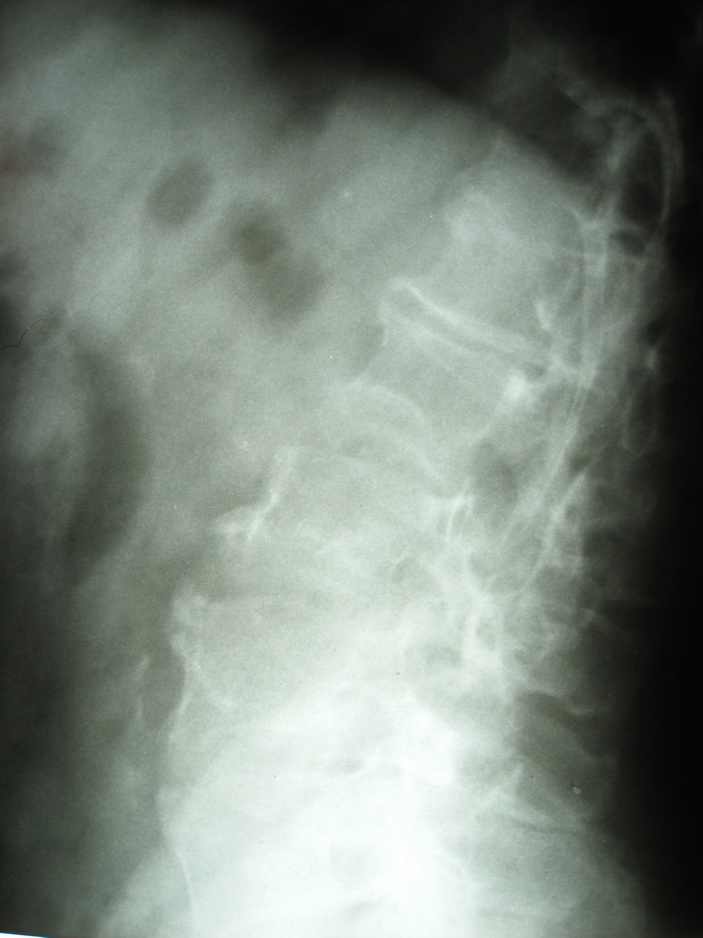

标题: X4179:腰椎会诊

请各位指点。

脊柱s形侧弯旋转,t12,l1.2看不清.请提供侧位片.

显然上部腰椎已是强直性表现.病因只有结合病史.前面的老师提到畸形性骨炎, 我认为可不考虑,因为没畸形性骨炎的主要表现,即骨体呈增大增宽的破坏和成骨.

脊椎成\"s\"形弯曲,椎体边缘骨质增生改变明显,考虑脊椎侧弯畸形伴退变

脊椎成"s"形弯曲,椎体边缘骨质增生改变明显,考虑脊椎侧弯畸形伴退变